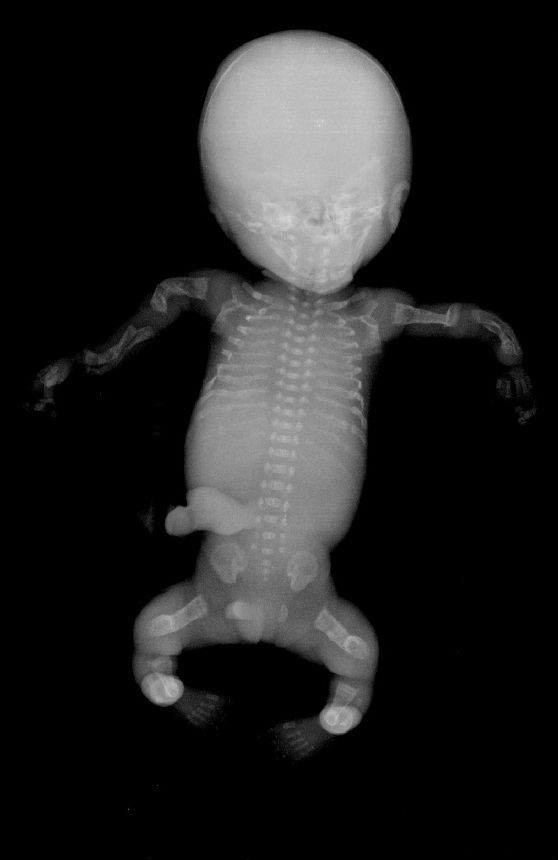

Quella che interessa dal punto di vista della diagnosi ecografica prenatale è l'Osteogenesi Imperfetta tipo II (OMIM 166210) caratterizzata da fragilità ossea con fratture multiple, micromelia severa dovuta alle fratture delle ossa lunghe, ipoplasia toracica severa a volte con fratture costali, ipomineralizzazione diffusa del cranio.  Ecograficamente si manifesta con ossa corte, ricurve e fratturate (le ossa fratturate si presentano angolate); ossa craniche scarsamente ossificate (tanto che la volta cranica può avere una ecogenicità simile a quella della linea mediana) con conseguente migliore evidenza e definizione delle strutture cerebrali e segno caratteristico la deformabilità della teca cranica.;  ipoplasia toracica con fratture costali; IUGR; movimenti fetali scarsi.